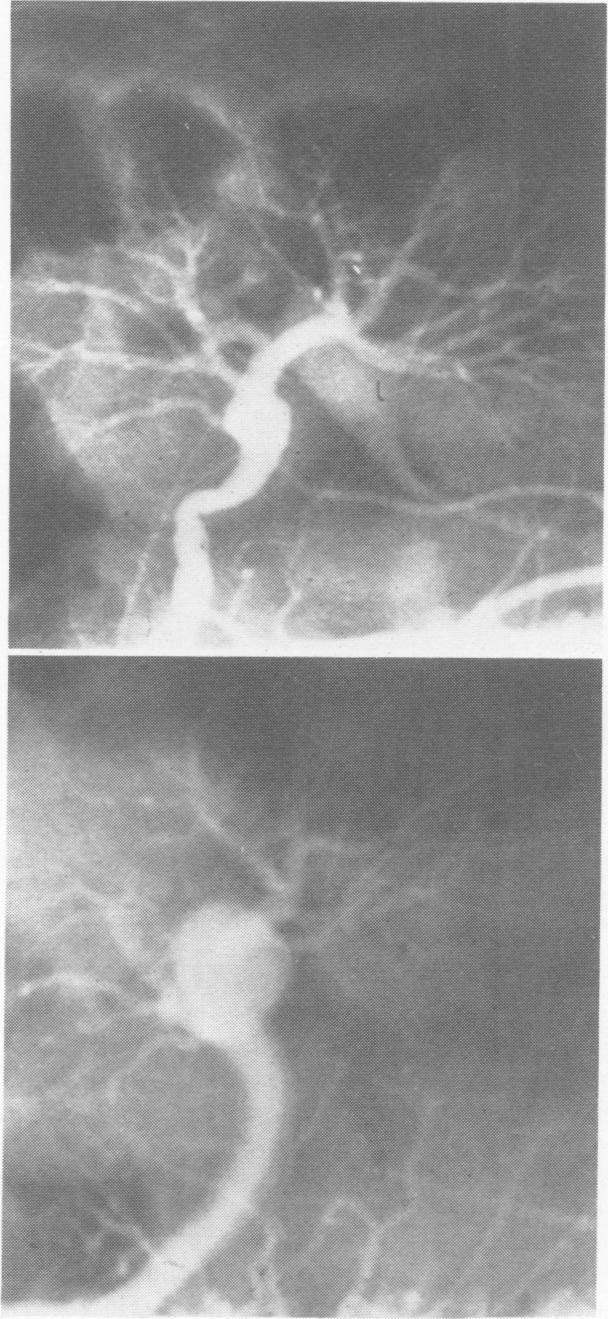

体外肾动脉重建。

Ex vivo renal artery reconstruction.

Ex vivo renal artery reconstruction and autotransplantation is a relatively recent addition to the surgical armamentarium for renal vascular hypertension. Ten consecutive patients were considered for this surgical therapy and form the basis of this communication. The patients were treated by a combination of methods including bilateral ex vivo reconstruction, unilateral in situ and contralateral ex vivo reconstruction, and unilateral ex vivo reconstruction and contralateral nephrectomy. Replacement of the diseased segment of the renal artery in all ex vivo reconstruction consisted of arterial autografts including hypogastric artery, splenic artery, common iliac, and external iliac artery. In the ex vivo reconstruction, the ureter was either left intact or was transected and reconstructed by standard ureterovesicle implantation. After surgery all patients became normotensive without antihypertensive medication. Although this is a relatively small series, the uniform good results in these patients with extensive disease suggest that ex vivo renal artery reconstruction is a safe and effective method of treatment. Thus, it should be more widely applicable, expecially in those patients with renal vascular disease who were previously thought to be inoperable or eligible for nephrectomy only.

体外肾动脉重建及自体肾移植是肾血管性高血压外科治疗手段中较新的一种。连续10例患者接受了这种外科治疗,并构成了本报告的基础。患者采用了多种方法联合治疗,包括双侧体外重建、单侧原位及对侧体外重建、单侧体外重建及对侧肾切除术。在所有体外重建中,肾动脉病变段的置换均采用自体动脉移植,包括腹下动脉、脾动脉、髂总动脉和髂外动脉。在体外重建中,输尿管要么保持完整,要么横断并通过标准的输尿管膀胱植入术进行重建。术后所有患者在未服用抗高血压药物的情况下血压恢复正常。虽然这是一个相对较小的系列病例,但这些患有广泛病变的患者均取得了良好的效果,表明体外肾动脉重建是一种安全有效的治疗方法。因此,它应该具有更广泛的适用性,特别是对于那些以前被认为无法手术或仅适合肾切除的肾血管疾病患者。